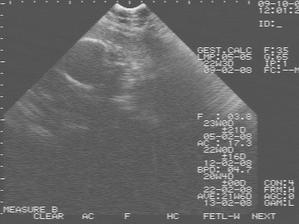

9.11.2007 jsme byly na biometrii a mame cca 952g -----